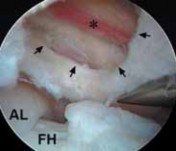

TECH FIG 2•

Arthroscopic view from the peripheral compartment of a right hip.

A.

A window (

arrows

) has been created through the thin medial capsule, exposing the iliopsoas tendon (

) anterior to the femoral head (

FH

).

B.

The tendinous portion is released with a basket.

C.

The final fibers are débrided with a power shaver.

D.

Through the capsular window (

) the tendon has been completely released, preserving the muscular fibers (

). The relation between the capsular window and the acetabular labrum (

AL

) and femoral

D

head (

) is identified. (Courtesy of J. W. Thomas Byrd, MD.)